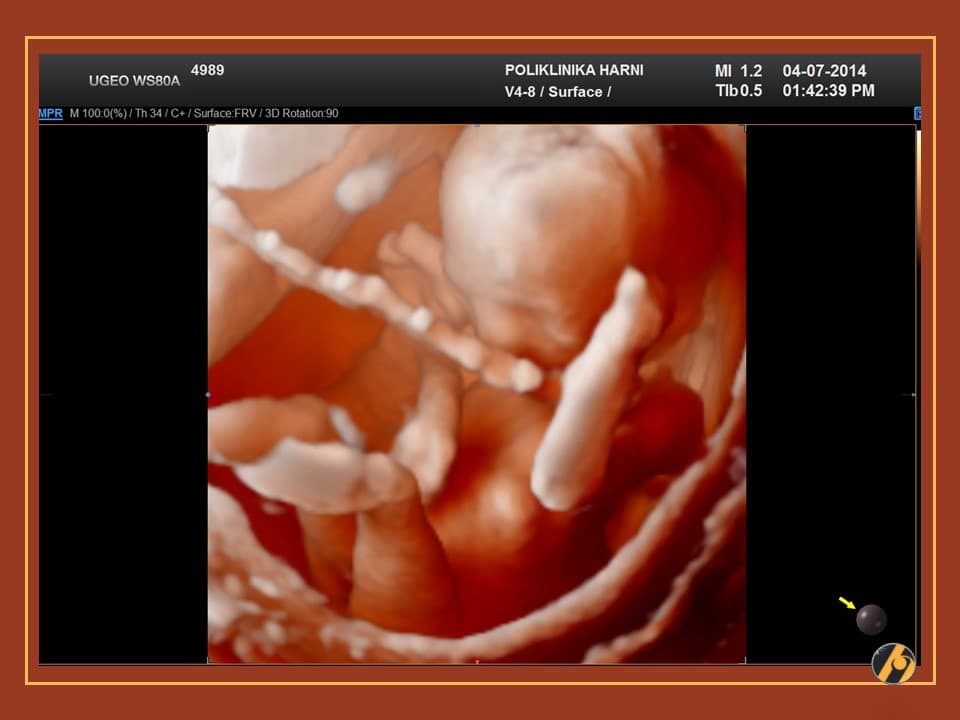

Nastavlja se finiji razvitak kože vaše bebe, koja je u ovo vrijeme tanka i prozirna i kroz koju se vidi mnoštvo krvnih žilica. Lanugo dlačice prekrivaju gotovo cijelu površinu kože bebe, a jasnije se ističu dlačice na obrvama. Počinje rasti kosa na glavi, a pigmentne stanice počinju stvarati crni pigment.

Razvijaju se daljnji centri okoštavanja i kosti, kao i koštana moždina koja preuzima funkciju žumanjčane vreće u stvaranju krvi djeteta. Zglobovi bebe su sve pokretljiviji, a beba s time i sve savitljivija. Sada vaša beba može svoje prstiće stisnuti u šaku.

Vaša beba guta amnijsku tekućinu koja ga okružuje, što pomaže sazrijevanju respiratornog sustava. Bebine oči su i dalje zatvorene, ali beba počinju reagirati na svjetlost izvan vaše maternice. Od ovog tjedna vaše će dijete početi čuti zvukove u vašem tijelu, poput otkucaja srca i trbuha.

Vaša beba dugačka je 10 - 12 cm, a teška 50 - 100 g.